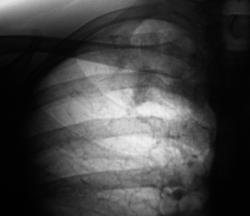

У пациента обнаружены МБТ, госпитализирован в туб. больницу, где проведено "стандартное лечение". После лечения произведено "контрольное" рентгенологическое исследование.

Сегодня, пациента планово направили в рентгеновскитй кабинет. Произведено стандартное исследование.

Какое мнение коллег будет по поводу последних трёх иллюстраций? Что это такое с полостью распада?

Большое спасибо за иллюстрацию. По моему здесь имеет место бронхогенное обсеменение из левого  легкого в правое. Вероятно и МБТ из этой полостушки, хотя и в правом легком инфильтрат неоднороден. А что Вас смущает в этой полости?

Меня не смущает ничено. Просто, как это ни странно, с учетом локализации, "ЭТО" оказалась туберкулома в весьма активном и агрессивном состоянии. Возможно, наступит "кавернизация" туберкуломы.